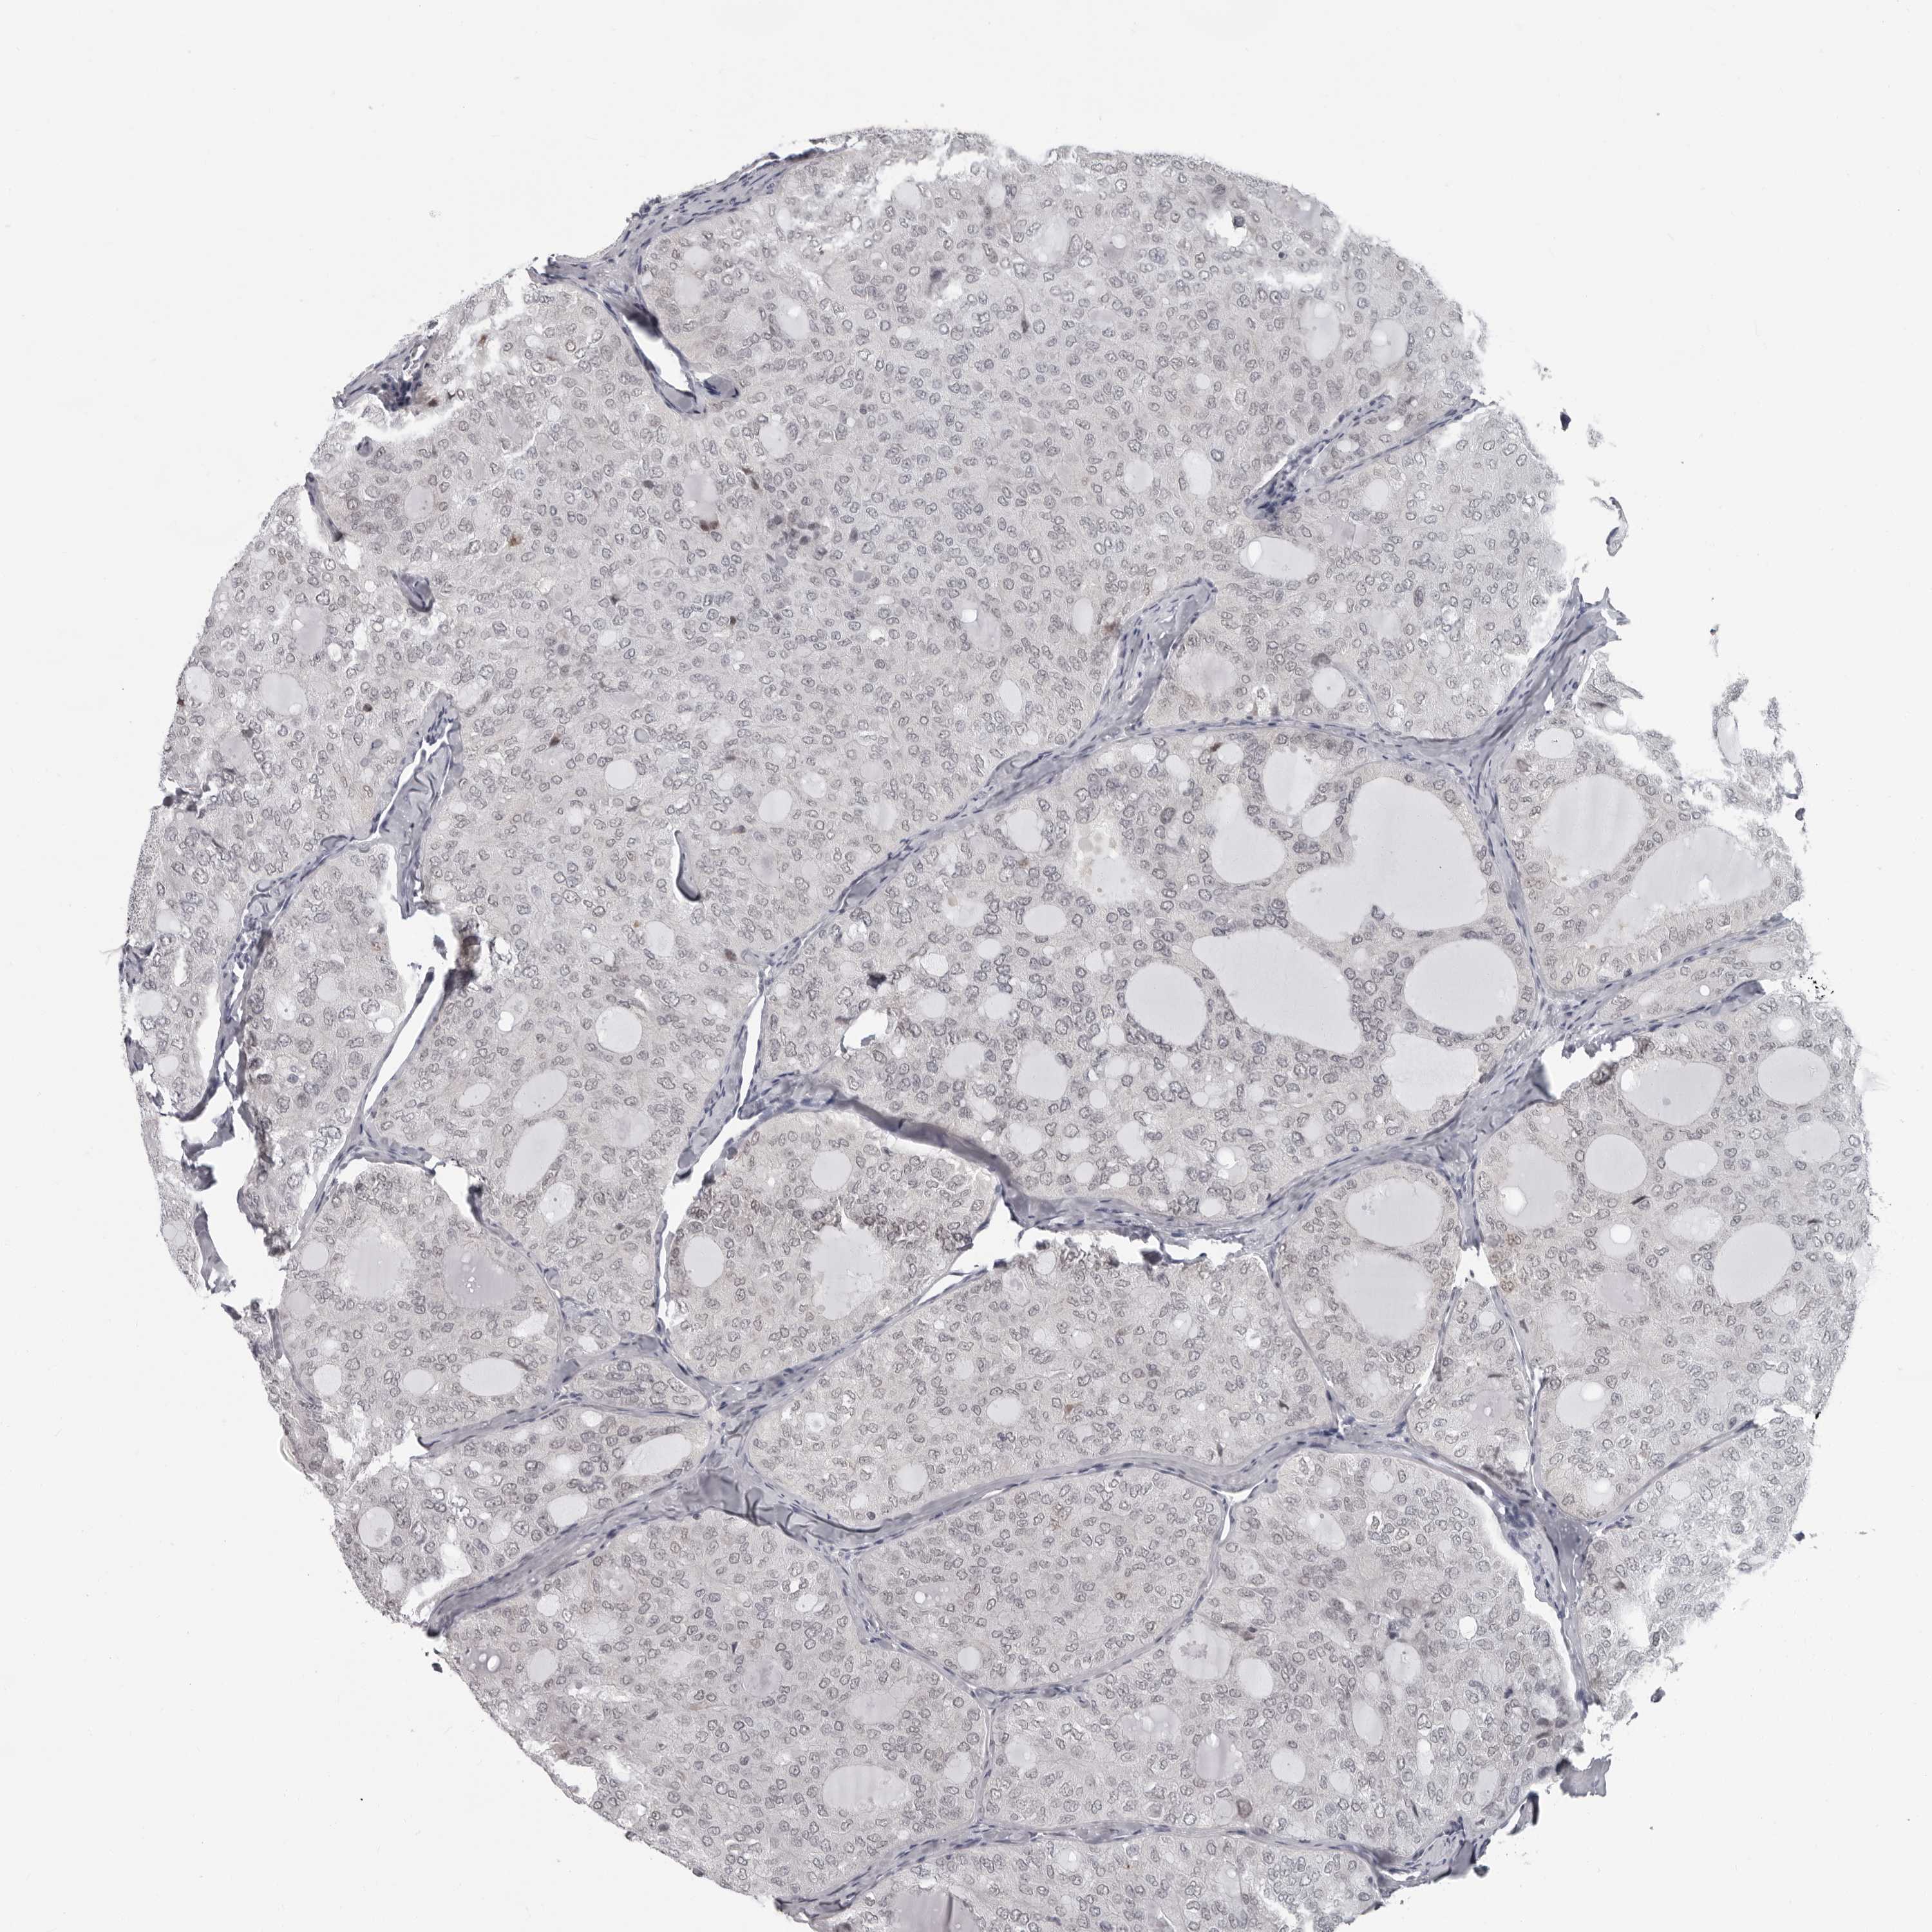

THYROID CANCER - Protein expressioni

A mouse-over function shows sample information and annotation data. Click on an image to view it in a full screen mode. Samples can be filtered based on level of antibody staining by selecting one or several of the following categories: high, medium, low and not detected. The assay and annotation is described here.

Note that samples used for immunohistochemistry by the Human Protein Atlas do not correspond to samples in the TCGA dataset.

Antibody stainingi

Antibody staining in the annotated cell types in the current human tissue is reported as not detected, low, medium, or high, based on conventional immunohistochemistry profiling in selected tissues. This score is based on the combination of the staining intensity and fraction of stained cells.

Each image is clickable and will lead to virtual microscopy that enables deeper exploration of all samples and also displays staining intensity scores, fraction scores and subcellular localization as well as patient and tissue information for each sample.

Antibody HPA028184

Staining

High

Medium

Low

Not detected

Intensity

Strong

Moderate

Weak

Negative

Quantity

>75%

75%-25%

<25%

None

Location

Nuclear

Cytoplasmic/membranous

Cytoplasmic/membranous,nuclear

Papillary adenocarcinoma, NOS

Follicular adenoma carcinoma, NOS